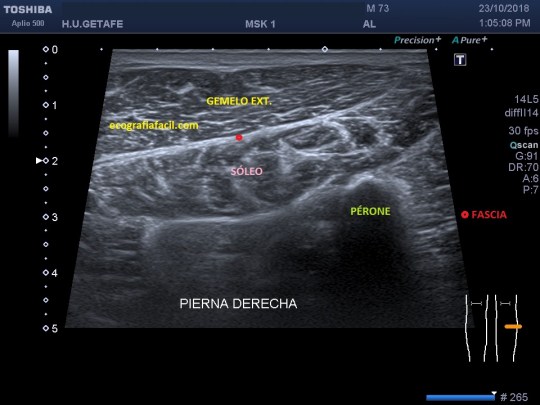

Criptorquidia: El testículo no descendido es una de las anomalías genitourinarias más comunes en niños. La mayoría de los testículos no descendidos son palpables y se localizan en el canal inguinal. Su aspecto ecogénico es normal, salvo si son vistos en la edad adulta, que pueden ser más pequeños y de ecogenicidad alterada. Objetivamente no van a estar en las bolsas y los vamos a encontrar donde marca el picto de la imagen 12. En ocasiones necesitan tratamiento quirúrgico. La flecha amarilla fina y alargada te marca la profundidad anómala debido a la piel y el tejido celular subcutáneo típico de la región inguinal, observa como cambia esta imagen respecto de cualquiera de las anteriores con los testes en sus bolsas.